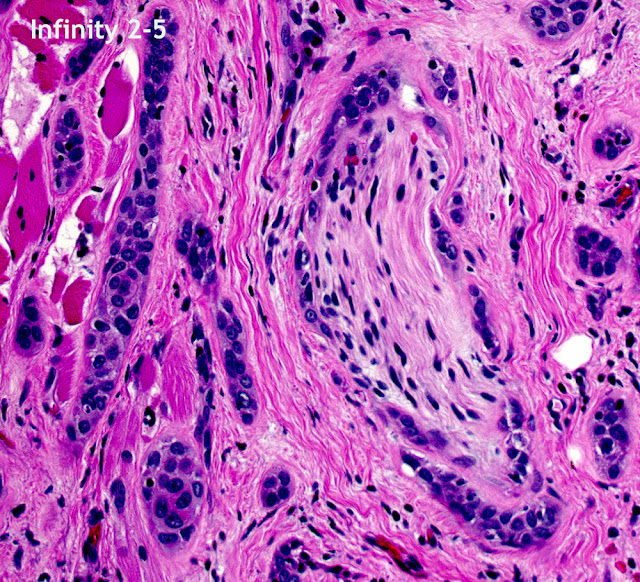

![]() |

| Microcystic Adnexal Carcinoma- Perineural captured with Infinity 2-5 camera. |

- 5 megapixel Infinity 2-5 CCD camerahas a peak quantum efficiency of 42% and a dynamic range of 58dB.